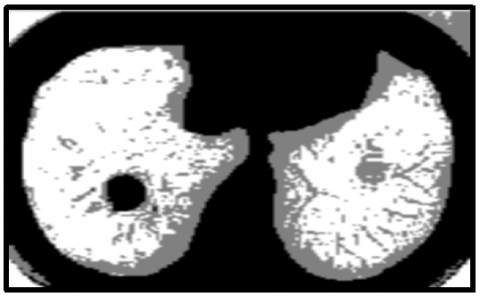

For clustering the input image, the KWFLICM algorithm is applied. After that, the tumor region is separated from the clustered output of the KWFLICM method using the histogram approach. When it comes to clustering results, the KWFLICM method performs faster than other FLICM algorithms and produces superior results when images contain outliers or salt and pepper noise. The KWFLICM segmentation and clustering image is displayed in Figure 8.

(a)

(b)

Figure 8. (a) KWFLICM clustered image; (b) segmented image